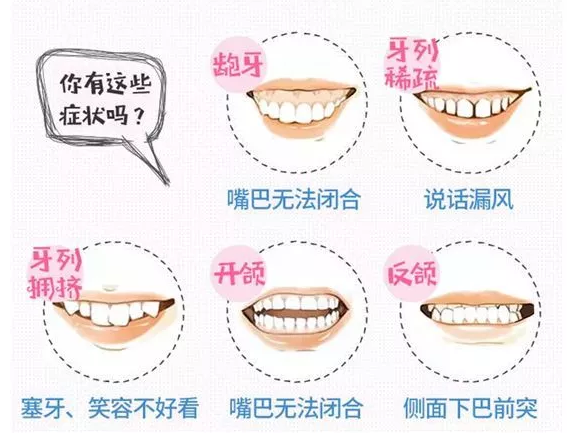

所谓瓜子牙就是前牙的两颗大门牙因为长期咬坚果类的东西会有几个浅窝,弧形缺损,不太平整,就形成了传说中的瓜子牙。》》》相关阅读:在廊坊女生龅牙怎么办?